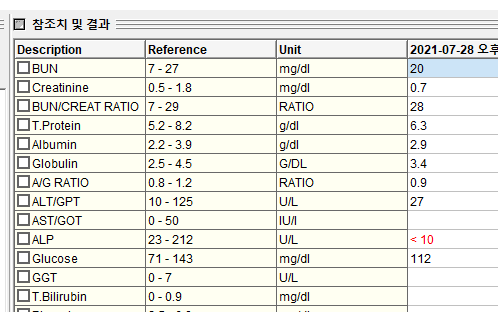

혈액검사 결과, 다행히도 복슬이의 신장 기능은 이상이 없었습니다.호흡곤란 증상이 발생한 이후, 초기에 발생한 호흡곤란 증상이 개선되는지가 중요합니다.

혈액검사 결과, 다행히도 복슬이의 신장 기능은 이상이 없었습니다.호흡곤란 증상이 발생한 이후, 초기에 발생한 호흡곤란 증상이 개선되는지가 중요합니다.